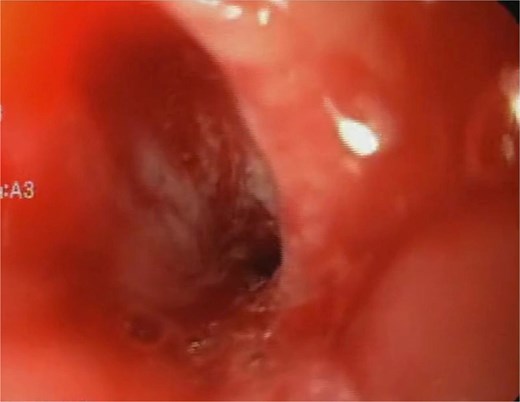

A 44-year-old female with no significant medical history underwent Roux-en-Y gastric bypass for grade III obesity (BMI 41). She presented with necrosis of the gastric pouch within the first 48 hours, leading to leakage of the gastrojejunal and jejunojejunal anastomoses. Esophagojejunal anastomosis and revision of the jejunojejunal anastomosis were performed, but the patient developed septic shock due to esophagojejunal anastomosis leakage, requiring 7 days in intensive care. Upon stabilization, she was referred to our service for endoscopic management of an esophagojejunal fistula. A 10 mm fistulous orifice was observed (Fig. 1), and EVAC therapy was initiated using a polyurethane sponge with an 8 Fr catheter at 125 mmHg continuous suction (Fig. 2). Six changes were made at 3–5-day intervals.

The placement of the catheter and sponge for EVAC therapy is observed.